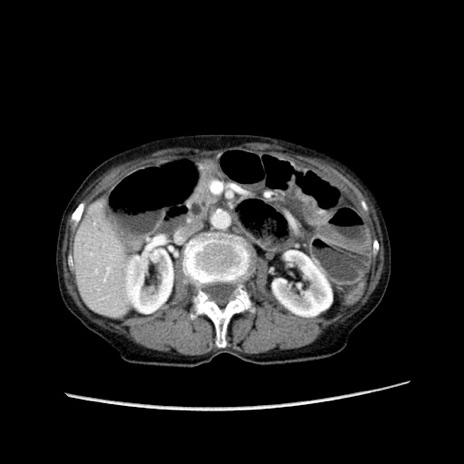

冠状断像

症例25(横断像)

【症例】80歳代女性

【主訴】胸のつかえ感

【現病歴】約9時間前に食後から胸のつかえた感じあり、嘔吐あり、来院。

【既往歴】胃癌(全摘)、胆摘、虫垂炎

【身体所見】心窩部に圧痛あり、反跳痛なし。

【データ】WBC 5700、CRP 0.05